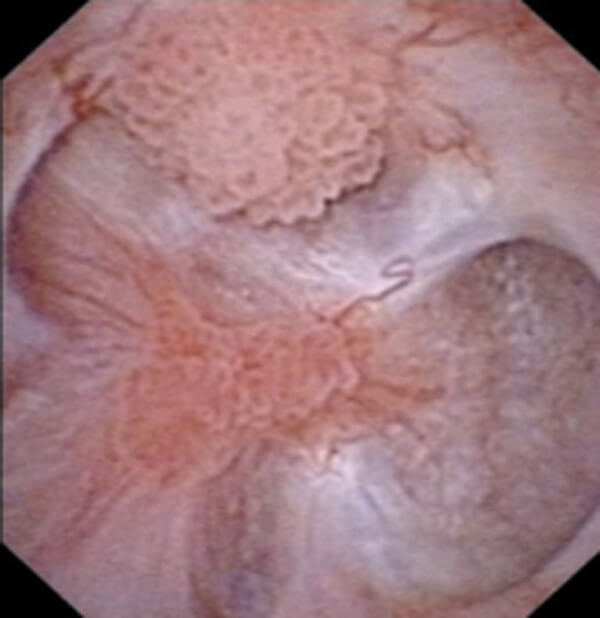

A 64-year-old man presents to the haematuria clinic with visible haematuria, on a background of a 40 pack-year smoking history and family history of bowel cancer in his sister at the age of 48. A CT was performed as part of his investigations (Figure 1).

Figure 1.

- This is a CT urography (CTU), or CT intravenous urogram (CT-IVU). Most CTU protocols consists of three phases; non-contrast, enhanced / nephrographic, and a delayed / excretory phase. The non-contrast phase is performed prior to contrast administration, the enhanced phase is taken 90-100 seconds after contrast administration and the delayed phase is taken 5-15 minutes after contrast has been given.

- The delayed phase of this CT has demonstrated a filling defect in the left renal pelvis, raising suspicions of UTUC. Other common differential diagnosis includes centrally located renal cancer, benign tumours (e.g. fibroepithelial polyps, nephrogenic adenomas), papillary necrosis, and blood clot.